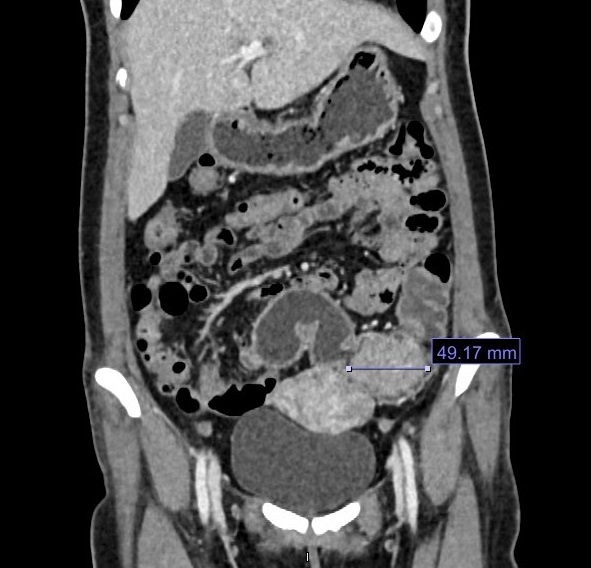

Hình ảnh CT (chụp cắt lớp) cho thấy có khối u gần 5 cm ở đại tràng.

BS Nguyễn Quốc Thái - Trưởng khoa Ngoại tiêu hóa, Trung tâm Nội soi và Phẫu thuật nội soi tiêu hóa - thăm khám trực tiếp và chỉ định nội soi đại tràng, chụp cắt lớp vi tính, phát hiện bệnh nhân có polyp đại tràng lớn khoảng 5 cm, chiếm hết lòng ruột. Trong quá trình nội soi, do khối u sần sùi bít lòng ruột và dễ chảy máu, ống soi không qua được. Kết quả giải phẫu bệnh phẩm là ung thư giai đoạn sớm rất sớm (Tis - giai đoạn 0). Đây là giai đoạn ung thư biểu mô tại chỗ (còn gọi là ung thư tại chỗ). Tế bào ung thư được tìm thấy ở niêm mạc hoặc mô đệm - những lớp trên cùng lót bên trong đại tràng hoặc trực tràng.